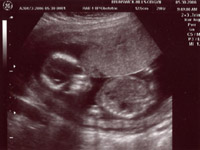

The boy parts :) |